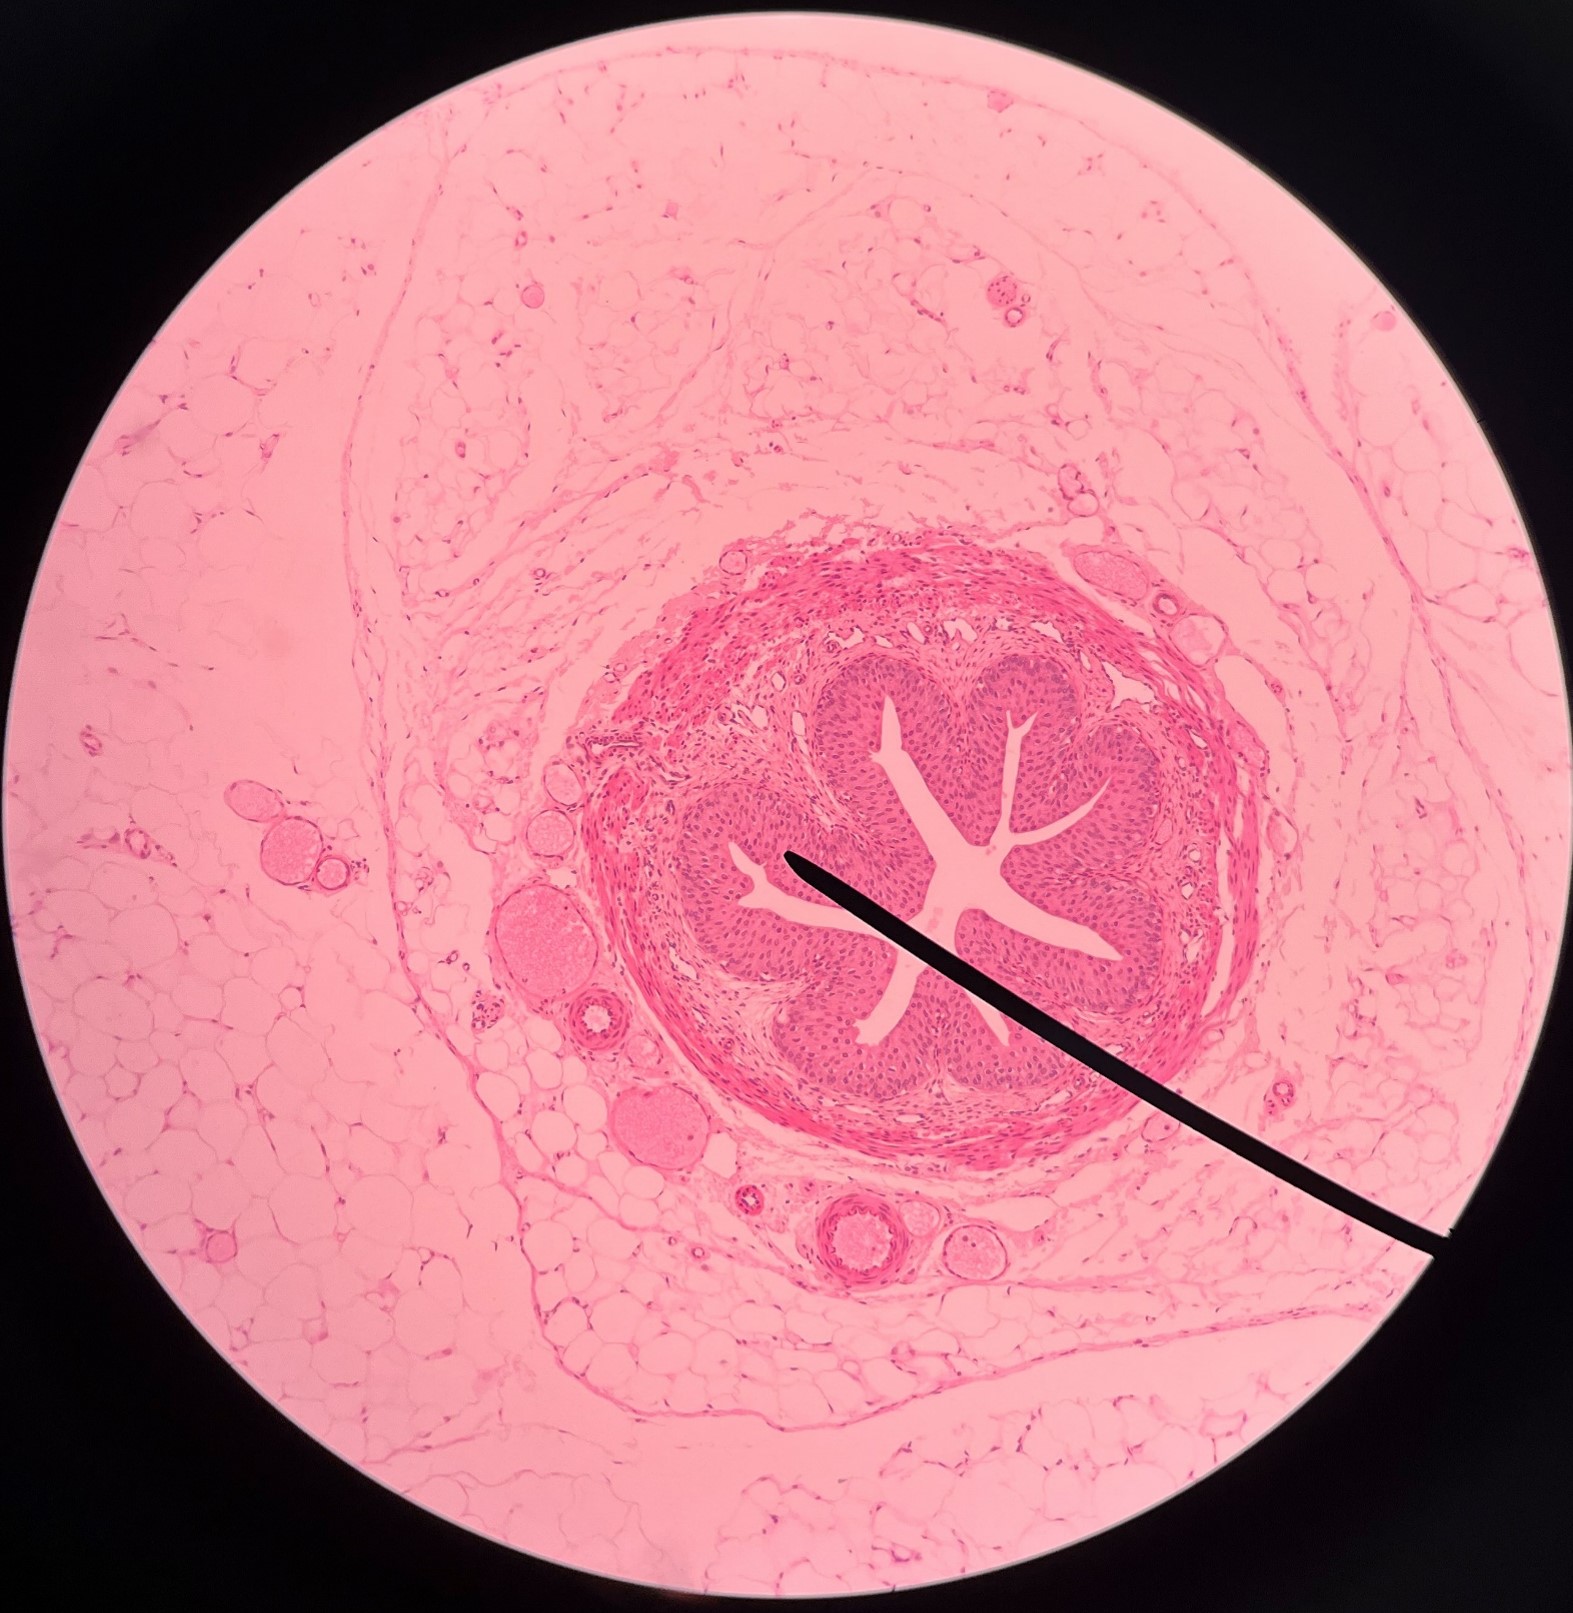

New cards

adventitia

• Slide histology of the ureter.

• The outermost layer of the ureter.

• Composed of connective tissue.

• Superficial to the circular layer of the muscularis.

• The outermost layer of the ureter.

• Composed of connective tissue.

• Superficial to the circular layer of the muscularis.

23

New cards

circular layer of muscularis

• Slide histology of the ureter.

• A smooth muscle layer of the ureter.

• Superficial to the longitudinal layer of the muscularis and deep to the adventitia.

• A smooth muscle layer of the ureter.

• Superficial to the longitudinal layer of the muscularis and deep to the adventitia.

24

New cards

longitudinal layer of muscularis

• Slide histology of the ureter.

• A smooth muscle layer of the ureter.

• Superficial to the mucosa and deep to the circular layer of the muscularis.

• A smooth muscle layer of the ureter.

• Superficial to the mucosa and deep to the circular layer of the muscularis.

25

New cards

mucosa

• Slide histology of the ureter.

• The innermost layer of the ureter.

• Composed of urothelium.

• Faces the lumen of the ureter and is deep to the longitudinal layer of the muscularis.

• The innermost layer of the ureter.

• Composed of urothelium.

• Faces the lumen of the ureter and is deep to the longitudinal layer of the muscularis.